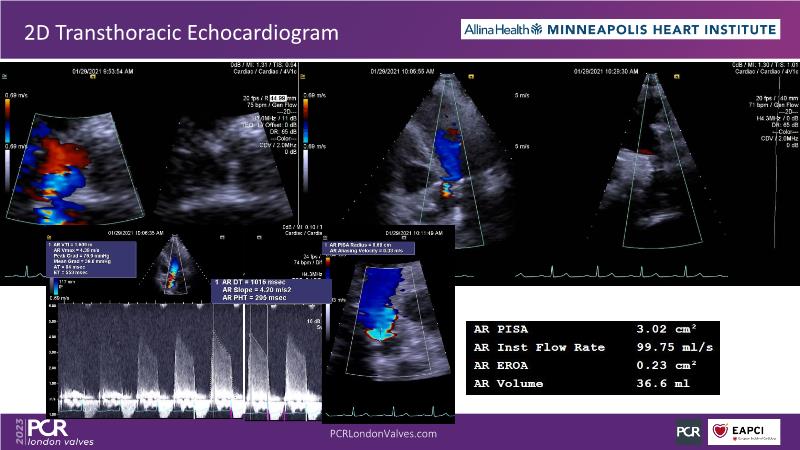

- To understand the challenges of imaging for aortic regurgitation and how it can lead to underdiagnosis